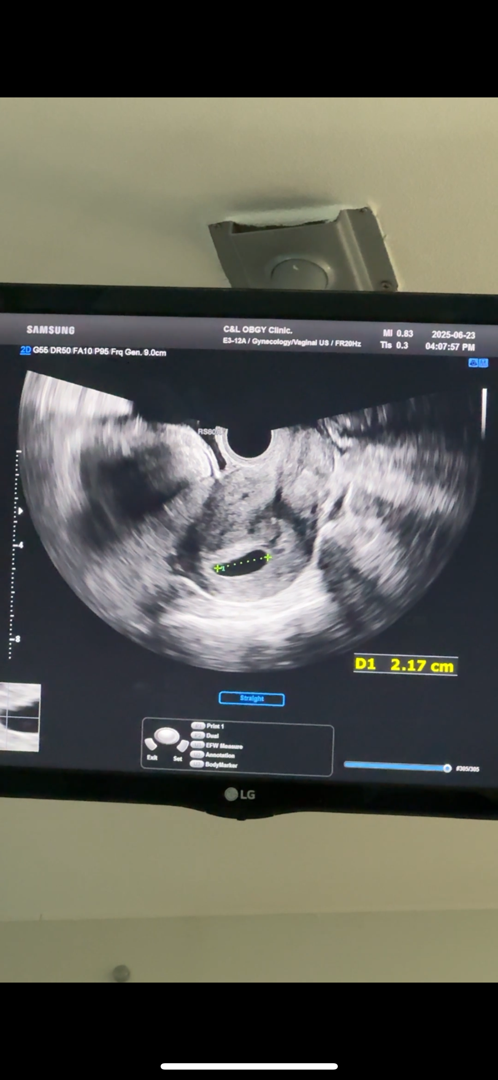

오늘 막생으로는 6주 1일차 저번주 초음파 상으로 계산했을때는 5주5일차입니다. 저번주 초음파 상으로 애기집이 0.4cm로 원장님께서 좀 작다고 해서 일주일 후에 보자고 하셔서 오늘 다시 병원을 갔는데 애기집은 2cm로 잘 컸다고 애기가 보일거 같다고 찾으셨는데 그냥 까맣게 보여서 원장님도 당황하시고 저도 우울해지고 원장님께서 이번주 금요일날 다시 와서 봐보자고 늦게 착상되서 늦게크는거일수도 있다고 걱정말라고 하시는데 저처럼 이러다가 보이셨던 분들 계실까요? 첫임신이라 긍정적인 생각을 하고 싶어도 너무 우울하고 눈물이 날거 같아요